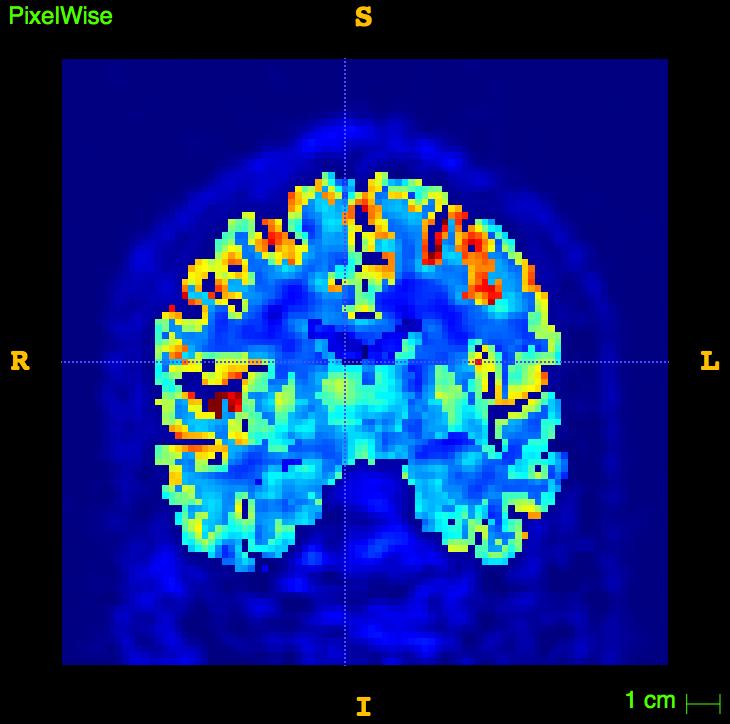

Glucose PET/MRI in MS

29 patients, 14 CIS/eRRMS and 15 RRMS underwent a PET/MRI with:

- MRI sequences: 3D T1, 3D FLAIR, 3D DIR

- 18F-Fdg PET in list-mode

The aim is to study the relationship between:

- Cortical Thickness

- WM/GM lesion number/volume

- aMRGlu